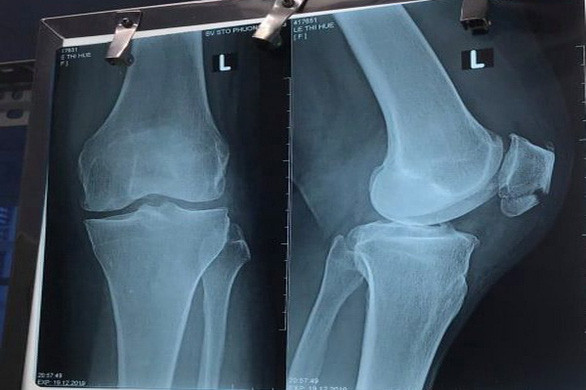

Phim chụp xương bánh chè của bà H. (Ảnh: TTO). |

Phim chụp xương bánh chè của bà H. (Ảnh: TTO).